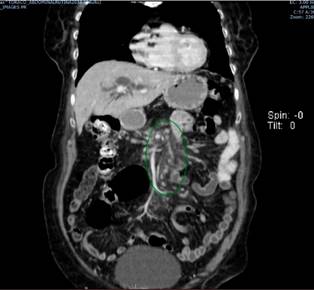

Se trata de una paciente de 72 años con cuadro clínico de obstrucción biliar secundaria a una masa en la cabeza del páncreas, cuyos estudios se describen a continuación: los niveles de bilirrubinas iniciales totales se encontraron en 12,32 mg/dL a expensas de la directa, que es de 10,8 mg/dL; tomografía de abdomen total que reportó neoplasia en la cabeza del páncreas, rodeando en 180° la vena mesentérica superior; confluente esplenoportal permeable; arteria hepática permeable; dilatación de la vía biliar intra- y extrahepática, y del conducto pancreático principal; aumento de la densidad de la grasa de la raíz del mesenterio con ganglios con ejes cortos (entre 5 mm y 6 mm) sospechosos por su realce; y lesión focal hepática en el segmento 6 de aspecto sospechoso para infiltración neoplásica, sin liquido libre (Figuras 1 y 2).